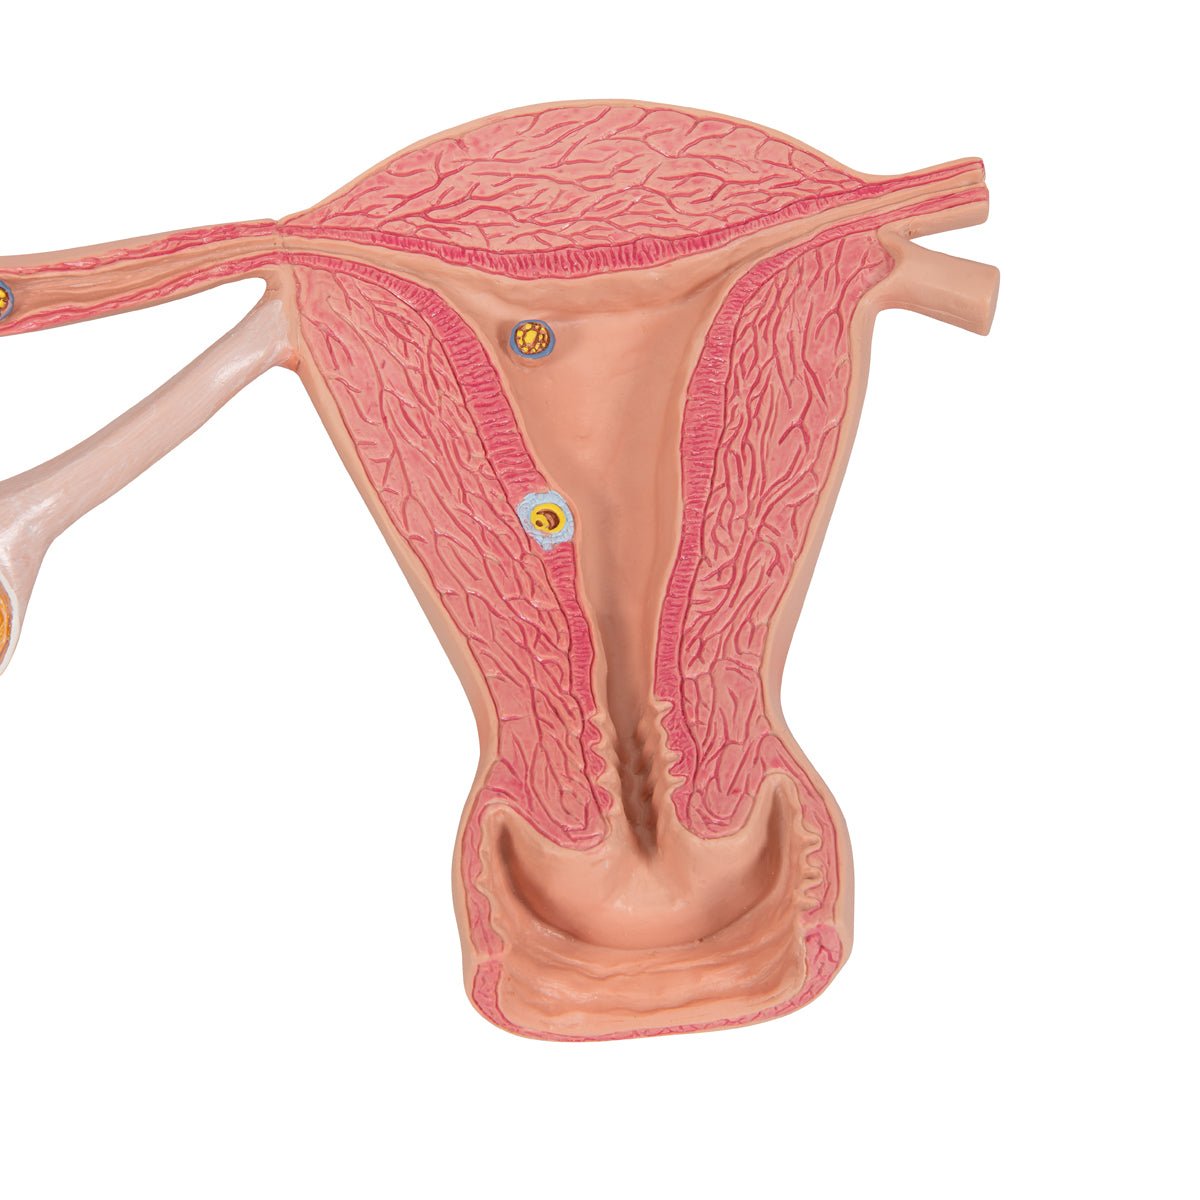

Salg af anatomiske modeller er det bærende element i eAnatomi, selvom vi også bruger mange ressourcer på at udvikle vores egne anatomiske materialer som fx plakater. Anatomiske modeller anvendes til forskellige formål og kan både vise afgrænset væv, organer samt organsystemer. Søger du en simpel model af knoglevæv eller måske en avanceret torso-model baseret på MRI teknologi, kan du finde det hele på eanatomi.com.